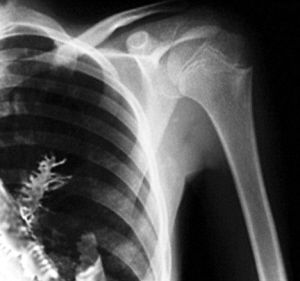

俄罗斯乌拉尔地区伊热夫斯克市日前惊曝一件咄咄怪事:一名28岁的当地男子因肺部异常疼痛、总是咳血而到医院检查。医生诊断他患了肺癌,于是为他实施了外科手术。让人匪夷所思的是,当医生切下这块“肺癌组织”时,竟然发现上面长着一棵长约5厘米的云杉小树苗!然而,对于这一“惊天发现”,世界各地的网友却提出了种种质疑。

据“乌德穆尔特癌症中心”主刀医生弗拉迪米尔·卡玛什夫介绍:“当时我眨了三次眼,确定看到了异物。接着我叫来助手,以便瞧个究竟。这棵5厘米长的小树苗后来被从患者体内取了出来。由于这棵云杉的针状树叶老是戳着这名男子肺部的毛细血管,导致他时常出血并且感到剧烈疼痛。”

患者希多金在术后接受记者采访时表示:“我从未想到过会有外来异物留在我的体内。”据医生们推测,希多金很可能是在不经意间吸入了一粒种子,后者随即在他的肺部生根发芽。

当这一近乎好莱坞科幻片情节的故事被报道后,有网友质疑这是一则“愚人新闻”。首先,树木种子处于人体肺部这样一个黑暗封闭的环境中,没有阳光,即使有营养成份的滋养,也根本不可能完成光合作用,因而也无法正常生长。